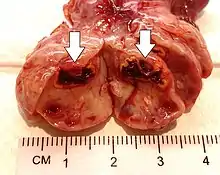

| Corpus luteum cyst | |